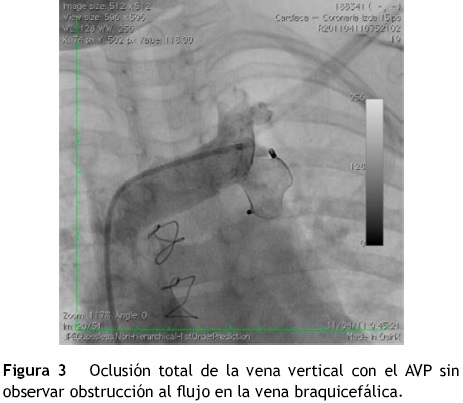

Se realizó el procedimiento avanzando una guía Amplatz extra stiff (Cook Medical, EE. UU.) a través de la vena cava inferior, aurícula derecha, vena cava superior, vena braquicefálica, vena vertical, aurícula izquierda y vena pulmonar superior izquierda. Se hizo oclusión con balón a nivel de la vena vertical y se realizó una inyección selectiva en la rama izquierda de la arteria pulmonar, observando en la levofase un adecuado retorno de las venas pulmonares a la aurícula izquierda (fig. 2A y B). Sobre la guía se avanzó un sistema de liberación de Amplatzer® 8 Fy a través de este se depositó un AVP de 16 mm en la vena vertical para su oclusión. Durante el procedimiento se administraron 50 U/kg de heparina.

En la angiografía de control se observó oclusión total de la vena vertical, sin obstrucción de la vena braquicefálica (fig. 3). La paciente no presentó complicaciones y fue dada de alta 24 h después de realizar el procedimiento.